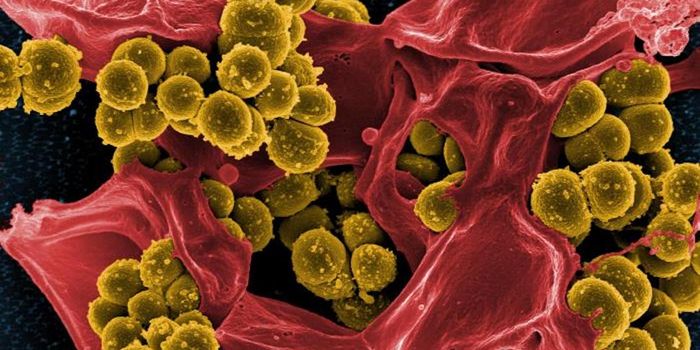

AUG 11, 2020Drug Discovery & DevelopmentScientists from Oxford University have shown that a single gene can make some strains of Staphylococcus aureus (the bact ...

SEP 17, 2021Cell & Molecular BiologyMRSA (methicillin-resistant Staphylococcus aureus) is a well known superbug, a pathogenic microbe that can cause serious ...